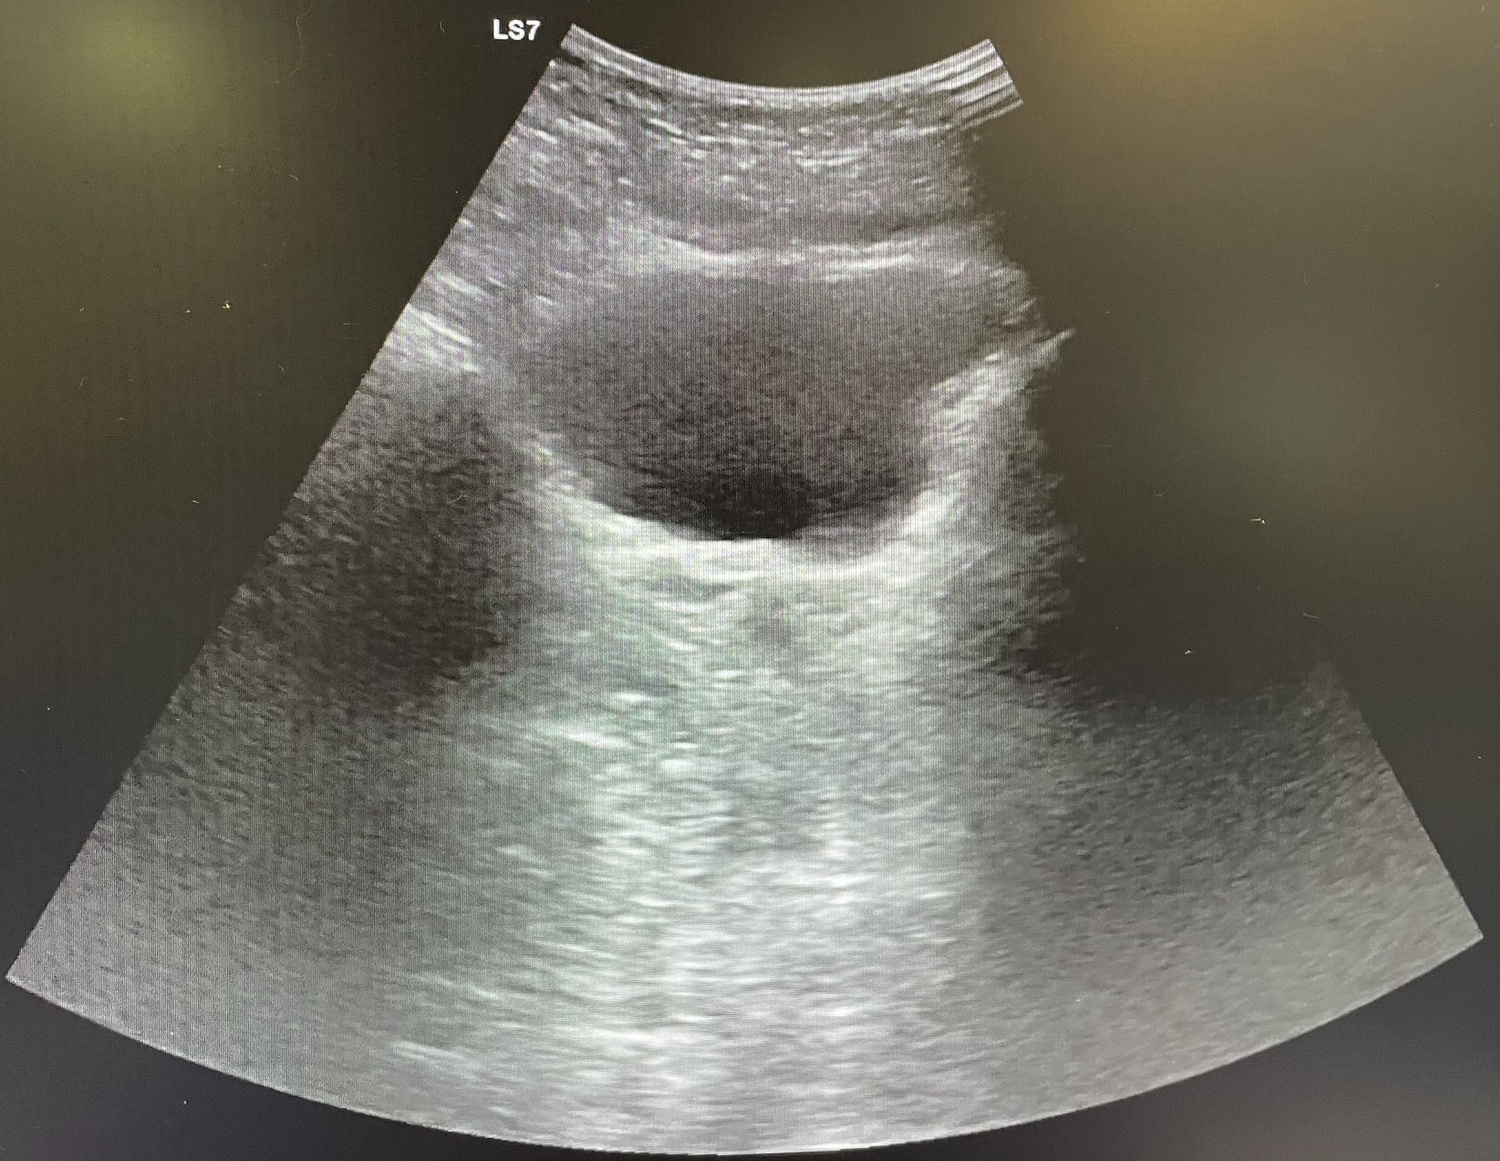

Se realiza analítica con aumento de reactantes de fase aguda (leucocitos 18.00 y PCR 108) y se indica ecografía abdominal que resulta no concluyente, por lo que se procede a alta.

Al día siguiente vuelve con la misma sintomatología, el dolor no cede con analgesia habitual. En la exploración Blumberg claramente positivo, se solicita analítica (leucocitos 13.000 y PCR 127) y se repite ecografía de abdomen que se sigue informando como no concluyente para apendicitis aguda.

Durante el ingreso la paciente presenta mejoría de la clínica, además de disminución de reactantes de fase aguda en analítica y ecográficamente sin peor evolución. Después de 3 días de ingreso se procede al alta a domicilio con antibioterapia oral y consulta de revisión ambulatoria.